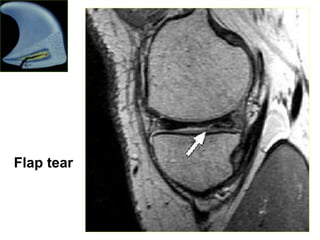

Flap tear

MRI giuùp xaùcñònh vò trí suïn raùch vaø daïng ñöôøng raùch: - Vò trí raùch suïn: 1/3 trong, giöõa hay ngoaøi - Daïng raùch: o Horizontal tear o Longitudinal tear o Radial tear o Flap tear o Bucket handle tear o Meniscocapsular separation